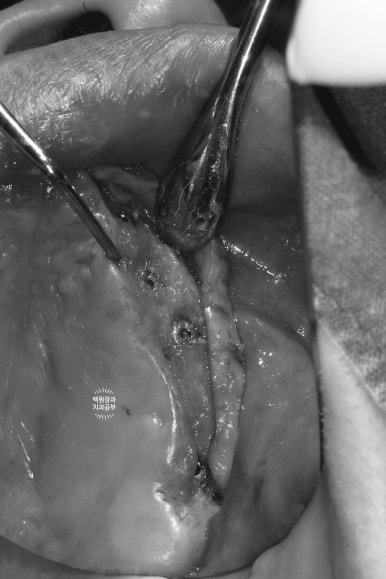

수술 하기 전 다시 봐도 정말.. 너무너무 얇은 잇몸뼈를 보실 수 있습니다.

칼 ridge라고도 부르는데... 손이 베일 것 같이 얇은 뼈 높이..

이런 경우 얇은 잇몸뼈는 일부 삭제 후 두꺼운 뼈 부위에 뼈이식을 하면서 임플란트를 위치시키게 됩니다.

나는 임플란트 장인이라는 생각을 갖고, 혼을 담아 임플란트 수술을 해드렸습니다.....

앞쪽에 식립되었던 4개의 임플란트는 역시나.. 얇은 잇몸뼈 밖으로 일부를 드러내고 있는 모습을 볼 수 있었구요..

이번에도 역시 덴티움 社의 합성골인 osteon III와 주변에서 채득했던 자가골을 이용하여 충분한 뼈이식을 해드렸습니다. 비용이 다소 추가되지만, 성공적인 뼈이식을 하기 위해서 같은 회사의 '흡수성 콜라겐 차폐막'은 반드시 사용되어야 합니다.

이것이 GBR (guided bone regeneration)의 기본 원리입니다.